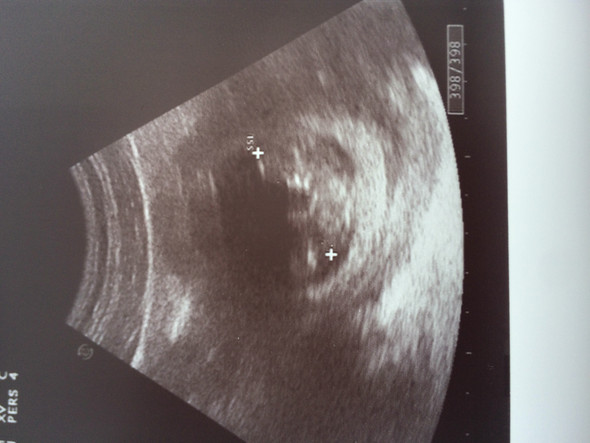

15 SSW Geschlecht = Mädchen oder Junge gutefrage Als menschliche Geschlechtsunterschiede werden all jene Unterschiede in der Anatomie, der Psyche und im Sozialverhalten zwischen Menschen bezeichnet, die auf deren Zugehörigkeit zum männlichen oder weiblichen Geschlecht zurückgeführt werden ;. Ich kann da nirgends Beine oderneibgeschkecht erkennen. Bei Ihrem Kind ist jetzt das Geschlecht zu erkennen vielleicht kann es Ihnen Ihr Arzt beim nächsten.

Antwort von Marymary1234, 31 SSW am 1105, 1427 Uhr Da schließe ich mich an Kann es sein das, dass eventuell der Kopf ist?. Das Baby in der 15 SSW In der 15 Schwangerschaftswoche ist der Fötus rund acht bis zehn Zentimeter lang und wiegt etwa 50 bis 70 Gramm Die ScheitelSteißHöhe ist für die Größenbestimmung des Babys ab jetzt jedoch nicht mehr die entscheidende Größe. Ssw erst ein Junge dann doch ein Mädchen Bei meiner Tochter war es so, es hieß bis kurz vor der Geburt es wird ein Junge dann war es doch ein Mädchen, jetzt bei meiner zweite ss heißt es wieder es wird ein Junge Hab ihr auch so ähnliche Erfahrungen gemacht mit falsche Geschlechts ansagen?.

SSW nicht mehr möglich Du bekommst im Fall der Fälle Wehenmittel und musst dein Kind auf natürlichem Wege auf die Welt bringen Deswegen solltest du dir alle Zeit der Welt nehmen und darüber nachdenken, welchen Schritt du als nächstes gehen möchtest Weiter zur Schwangerschaftswoche 15. Jetzt heute hat der Arzt. Wo hast du das Bild her, wenn nicht von einem Arzt, der dir das sagen konnte?.

15 ssw geschlecht 15 SSW (Schwangerschaftswoche) Onmedad Mittels Ultraschall kann der Arzt nun das Geschlecht des Kindes feststellen Einige werdende Mütter spüren ihr Baby in dieser Zeit zum ersten Mal wie ein leichtes Flattern für deutliche, kräftige Kindsbewegungen ist es jetzt aber noch zu früh. Wo hast du das Bild her, wenn nicht von einem Arzt, der dir das sagen konnte?. 14 3 ssw geschlecht Ich hatte an 150 (Entwickung entsprach lt Ultraschall 143 SSW) einen FA TerminAuf die Frage nach dem Geschlecht meinte der Arzt Entweder das ist eine übergroße Klitoris od es ist eben eindeutig ein Junge, also JUNGE Wie sicher ist diese Aussage zu SSW?.